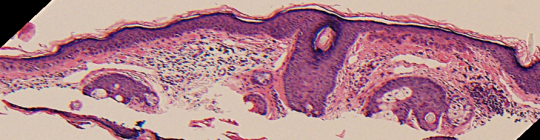

VA35: Left Temple, Actinic Keratosis, Hypertrophic

- White arrows indicate return to dermal collagen texture and reflectivity

VA35: Left Temple, Adjacent, Normal